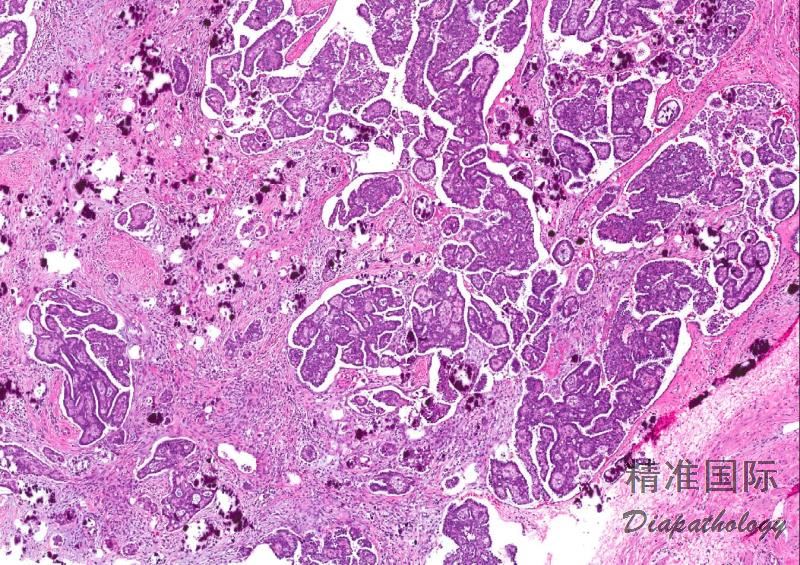

常累及双侧卵巢,呈细乳头生长方式;

特征性改变是各种类型的间质浸润,如单个细胞、不规则小细胞巢杂乱浸润间质;微乳头或大乳头周围围以无上皮衬覆的空隙;不同浸润方式可同时存在;

相当一部分低级别浸润性癌伴有浆液性交界性肿瘤/非典型增生性浆液性肿瘤;

砂粒体常见。